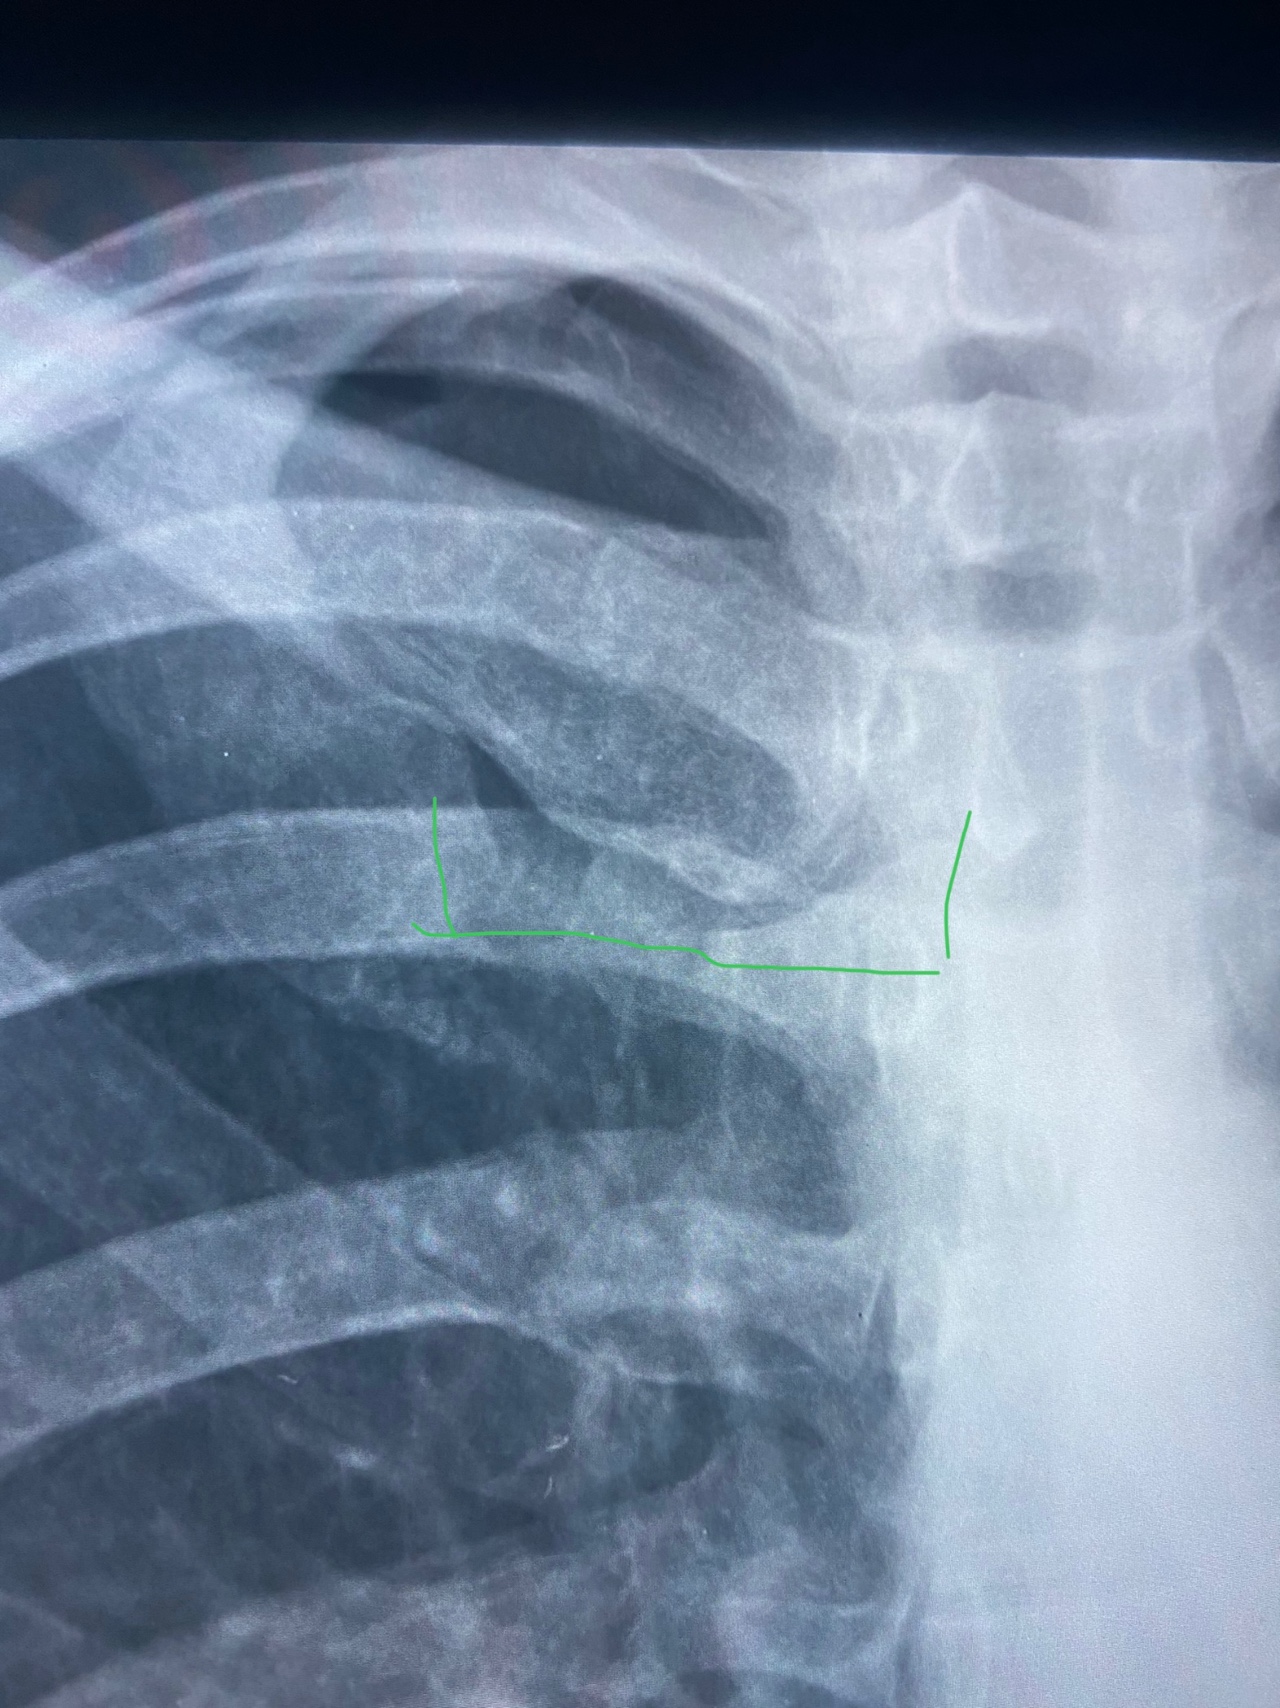

Медицина и диагностика: Аномалии ребер на рентгене